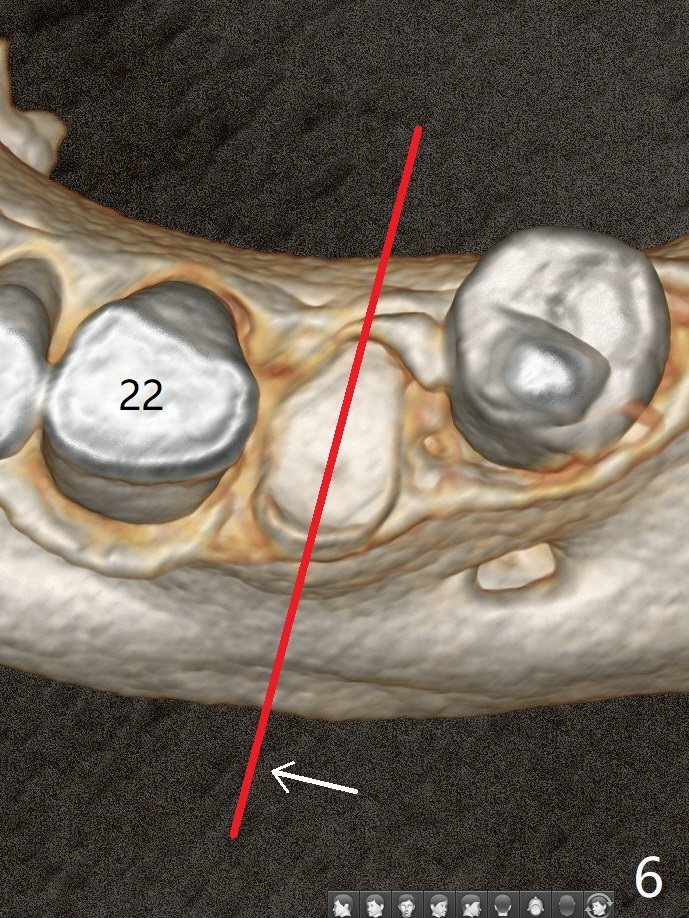

A 52-year-old man chooses to take care of the teeth #21 and 29 first due to finance (Fig.1). The implant diameter should not be too large because of the moderate mesiodistal space (Fig.2,3). Since the buccal plate of #21 is indistinct (socket shield will be done), the implant should be a little more lingually placed than the design in Fig.3, although the implant placement level seems to be acceptable. Socket shield seems to be necessary.